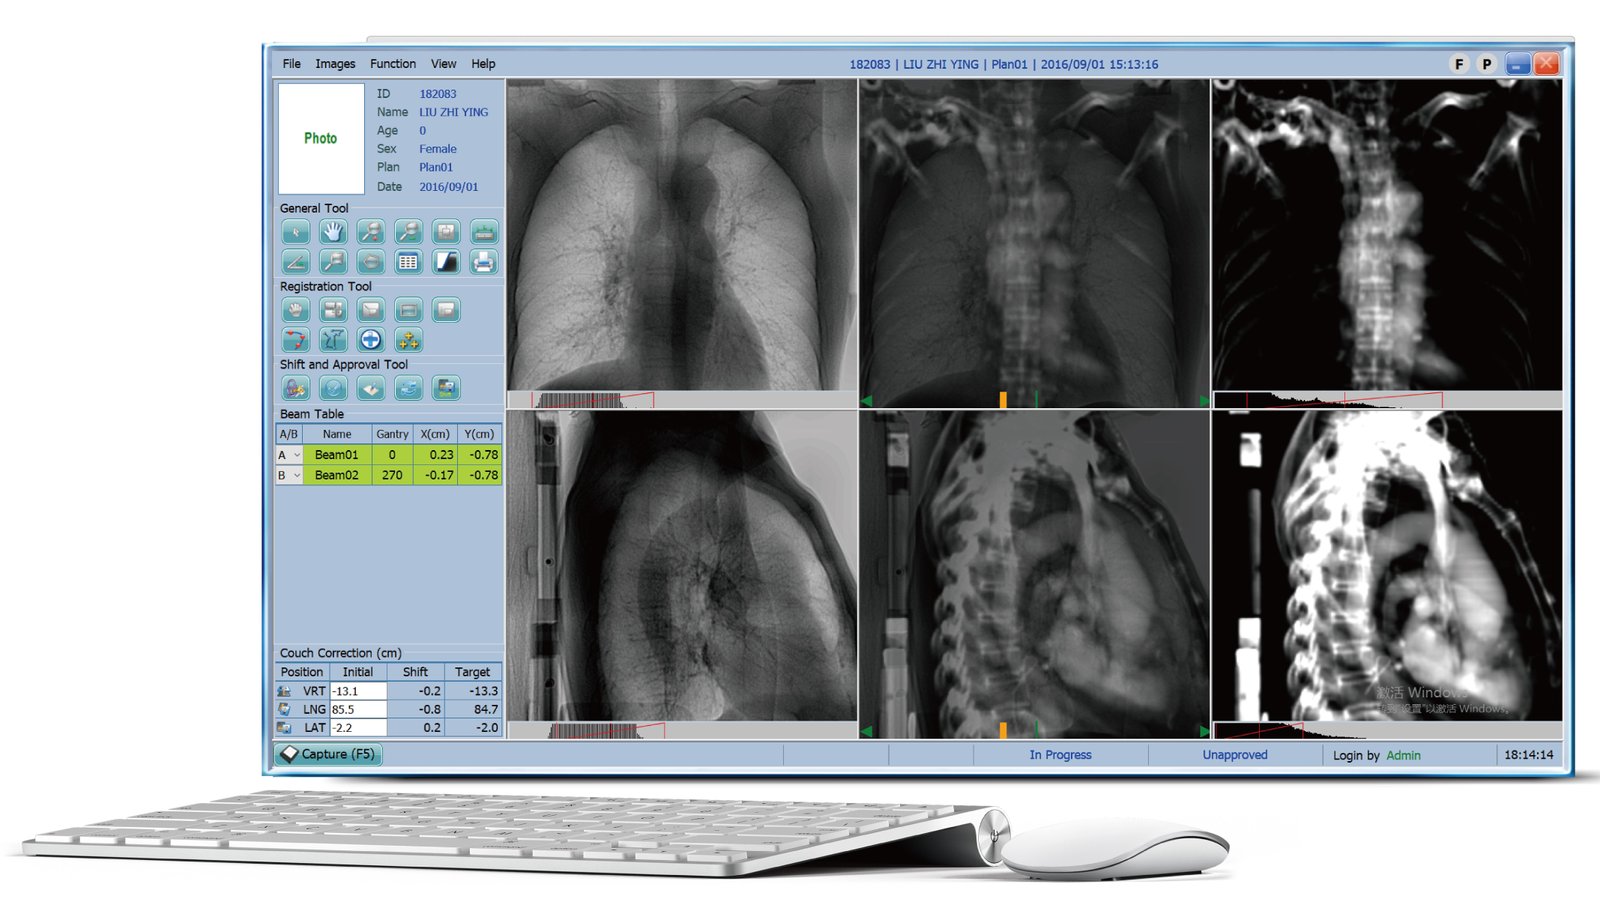

TiGRT-IVS

The clear MV-level verification image has a resolution of up to 2816X2816. Not only are the bony markers clear, but the soft tissue information is also very rich. It is matched with the Ai fast registration algorithm for accurate positioning, making patient positioning easier and more efficient.